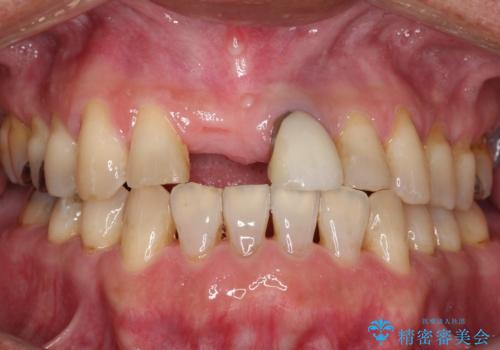

[根管治療・セラミッククラウン] 前歯の痛み・見た目を改善したい

![[根管治療・セラミッククラウン] 前歯の痛み・見た目を改善したいの症例 治療前](https://seimitsushinbi.jp/wp/wp-content/uploads/2021/10/27aece2ee2a0fb95849ae035eabf5926-500x350.jpg?v=1633830098)